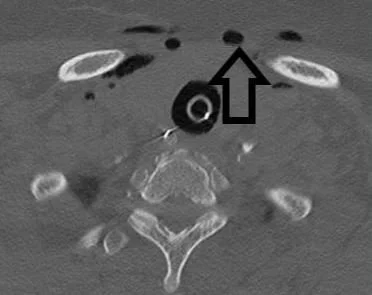

A 73 y.o. woman with a hx of stroke, comes in with altered mental status

she is intubated and scanned. What do you see?

hint: there is air where it does not belong

Our patient had an air embolus caused by IV insertion

air appears similar to the air in the trachea